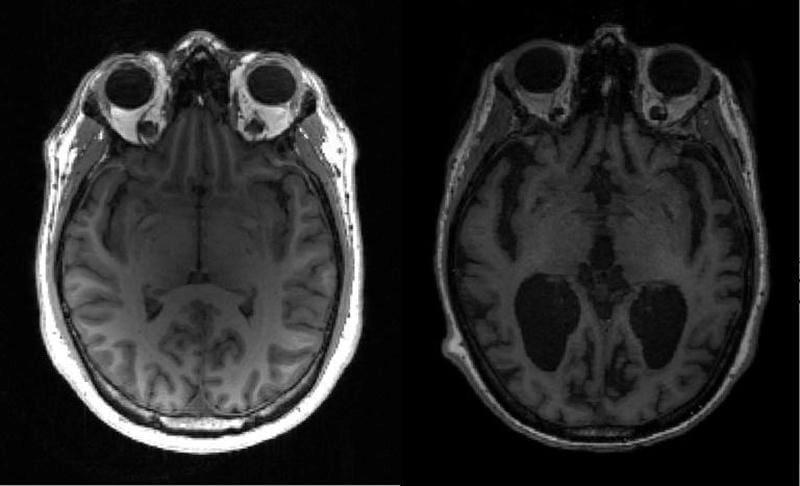

Khi những hình ảnh bệnh alzheimer đầu tiên được công bố, cả thế giới rúng động trước sự thật đáng sợ về căn bệnh này. Những bức ảnh mô tả sự teo nhỏ của não bộ, những mảng bám bất thường và sự thay đổi cấu trúc thần kinh khiến nhiều người không khỏi ám ảnh. Đây không chỉ là hình ảnh y học khô khan mà còn là lời cảnh tỉnh cho cộng đồng về căn bệnh cướp dần ký ức của hàng triệu người mỗi năm.

Bộ sưu tập hình ảnh bệnh alzheimer dưới kính hiển vi cho thấy sự khác biệt rõ rệt giữa não bộ khỏe mạnh và não bộ mắc bệnh. Những bức ảnh cận cảnh làm lộ rõ mảng amyloid và sợi thần kinh xoắn bất thường, nguyên nhân chính gây suy giảm trí nhớ. Mỗi bức ảnh đều kể một câu chuyện đau lòng, khắc họa hành trình từ quên lãng nhẹ đến mất hoàn toàn khả năng nhận thức của người bệnh.